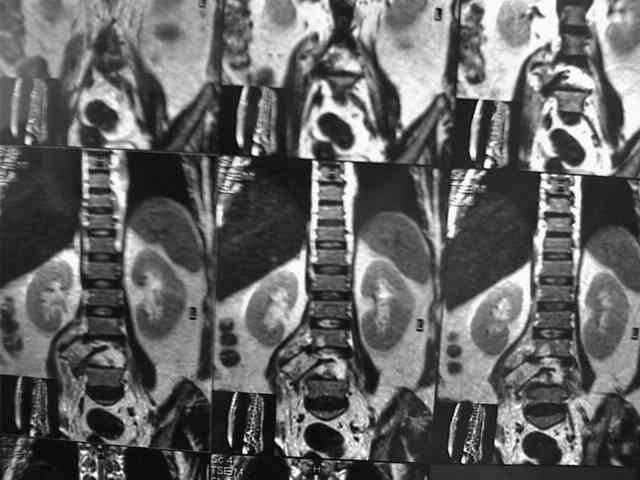

При этой картине удивительно еще то, что у нее нет никаких двигательных и тазовых нарушей.. Жалобы только на боли в спине. Движения и чувствительность в полном объеме. Никаких повреждений сосудистых магистралей также нет. Только изолированный перелом L5 со смещением тела позвонка в мягих тканях (забрюшинном пространстве). Остистый отросток на месте.

В приложении - МРТ.